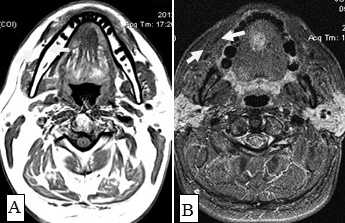

Не возникало сложностей в выявлении опухолевых узлов Т3, Т4 стадий, имевших все отмеченные выше признаки в различных сочетаниях в 36 исследованиях (рис. 11). Из 50 обследованных с помощью МСКТ и МРТ пациентов у 26 (52,0%) были выявлены метастазы в лимфатических узлах шеи. Поражались преимущественно лимфатические узлы I-II уровня. Признаками метастаза плоскоклеточного рака в лимфатических узлах были: увеличение размера лимфатического узла более 1,0 см, изменение формы лимфатического узла с бобовидной на округлую, структурные нарушения в узле, нечеткость наружных контуров узла, уплотнение окружающей жировой ткани на КТ или изменение сигнала на МРТ.

Большинство пораженных метастазами лимфатических узлов имели размеры более 1,0 см, округлую форму (рис. 12). Внутривенное контрастирование при оценке изменений в лимфатическом узле являлось обязательным условием для уточнения внутренней структуры и выявления зон некроза. В результате гипоксии и распада ткани формируется центральная зона некроза, не накапливающая контрастный препарат при внутривенном болюсном усилении. При этом отмечается повышение плотности в периферических отделах лимфатического узла (рис. 13).

Рис. 13. Пациентка К.,64 года. МСКТ ротоглотки, шеи в аксиальной проекции с внутривенным болюсным контрастированием. Рак языка с метастазами в лимфатические узлы средней яремной группы. Отмечается контрастирование пораженных лимфатических узлов по периферии, низкой плотности центральная зона некроза (стрелки). Билатеральное поражение